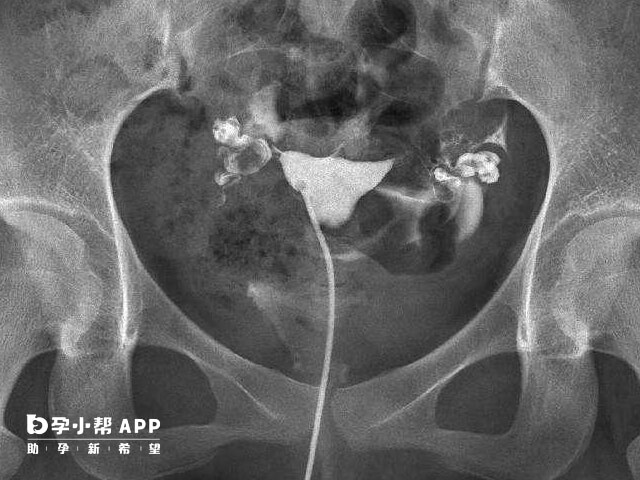

輸卵管堵塞患者通常無明顯症狀,部分患者可能出現下腹部疼痛、經量異常、發熱等症狀。嚴重時,可能引起白帶增多、全身無力、不孕、異位妊娠等併發症。一般而言,輸卵管堵塞很難通過自查診斷。患者應及時前往醫院就診。輸卵管可以說是女性很重要的生殖器官,在很多朋友知道在不孕症患者當中因為輸卵管因素無法懷孕的情況大約佔到三分之一以上,這樣一個比例,讓很多備孕不懷孕的朋友擔心自己可能就是因為輸卵管問題而無法懷孕。其中輸卵管堵塞是最主要的一個因素,所以說對於很多的女性來說要學會自己檢查輸卵管是否堵塞,這樣可以更好的懷孕。

輸卵管堵塞4個自查方法分別是看自己是否白帶增多、月經紊亂、經常性會出現腹痛、痛經嚴重,這幾點是臨床上面所總結的,建議姐妹們可以進行參考。